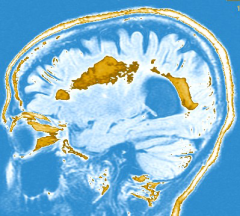

MRI of the brain showing multiple lesions

A Scenario: Meghan is a 22-year-old graduate student who is sent to the neurology office by the student health clinic with a chief complaint of pain and blurred vision in one eye. The neurological exam reveals decreased visual acuity in that eye and abnormal responses of the pupil to bright light. An MRI of the brain shows multiple lesions in the regions of the brain that carry connections, the cerebral “white matter.” In this MRI some of these lesions show enhancement with MRI contrast.